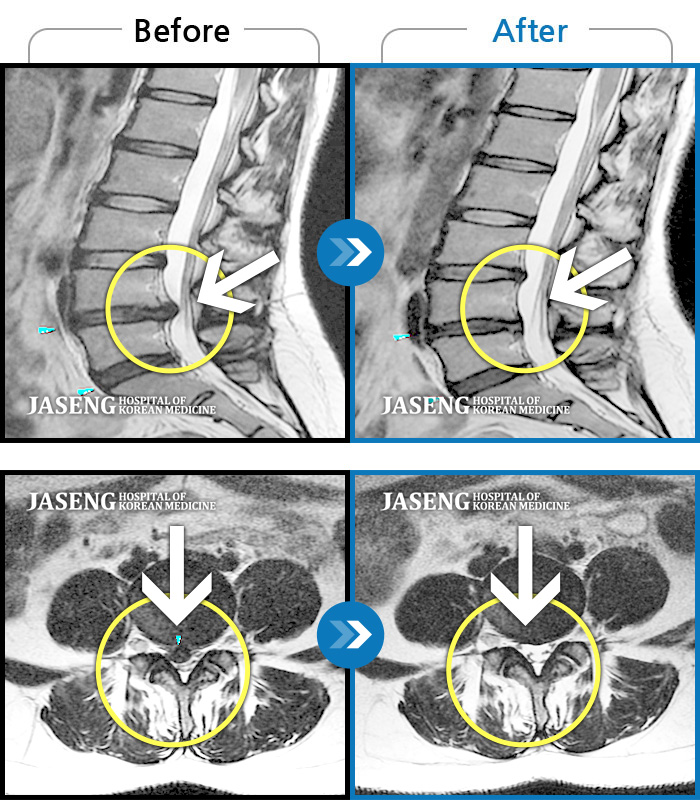

허리디스크

보라매 · 왕오호 원장

허리 통증, 똑바로 서려고 하거나 걸을 때 양쪽 허벅지와 고관절 시큰거림

촬영시기

2017.06.07 ~ 2018.04.17